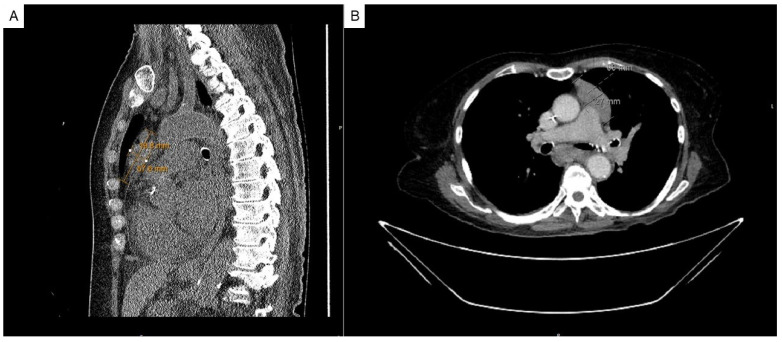

Case presentation: A 75-year-old woman was incidentally found to have a concomitant mediastinal mass and peripheral leukopenia with absent granulocytes and monocytes. Bone marrow assessment was notable for a hypocellular marrow (<10%) with absent granulopoiesis and monopoiesis. Chest CT demonstrated a large lobulated anterior mediastinal mass, for which the patient underwent a video-assisted thoracoscopic thymectomy. Pathological evaluation of the mediastinal mass specimen revealed a type B2 thymoma. A tentative diagnosis of thymoma-associated PWCA was made, and the patient was started on cyclosporine/granulocyte-colony stimulating factor (G-CSF)/filgrastim therapy. Despite promising marrow recovery, she developed several comorbidities and had a leukemoid reaction, provoking concern for immune reconstitution following prolonged neutropenia and subsequent treatment. She passed away on post-operative day 15, and the results of a post-mortem bone marrow examination were consistent with granulocytic hyperplasia.